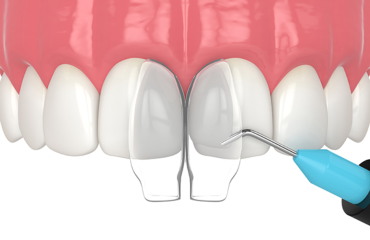

Parodontologie

Nos soins de parodontologie ciblent efficacement les maladies des gencives grâce à des traitements avancés. Nous prenons en charge la gingivite, la parodontite et d’autres problèmes liés aux gencives, pour une santé bucco-dentaire optimale et des gencives en pleine santé.